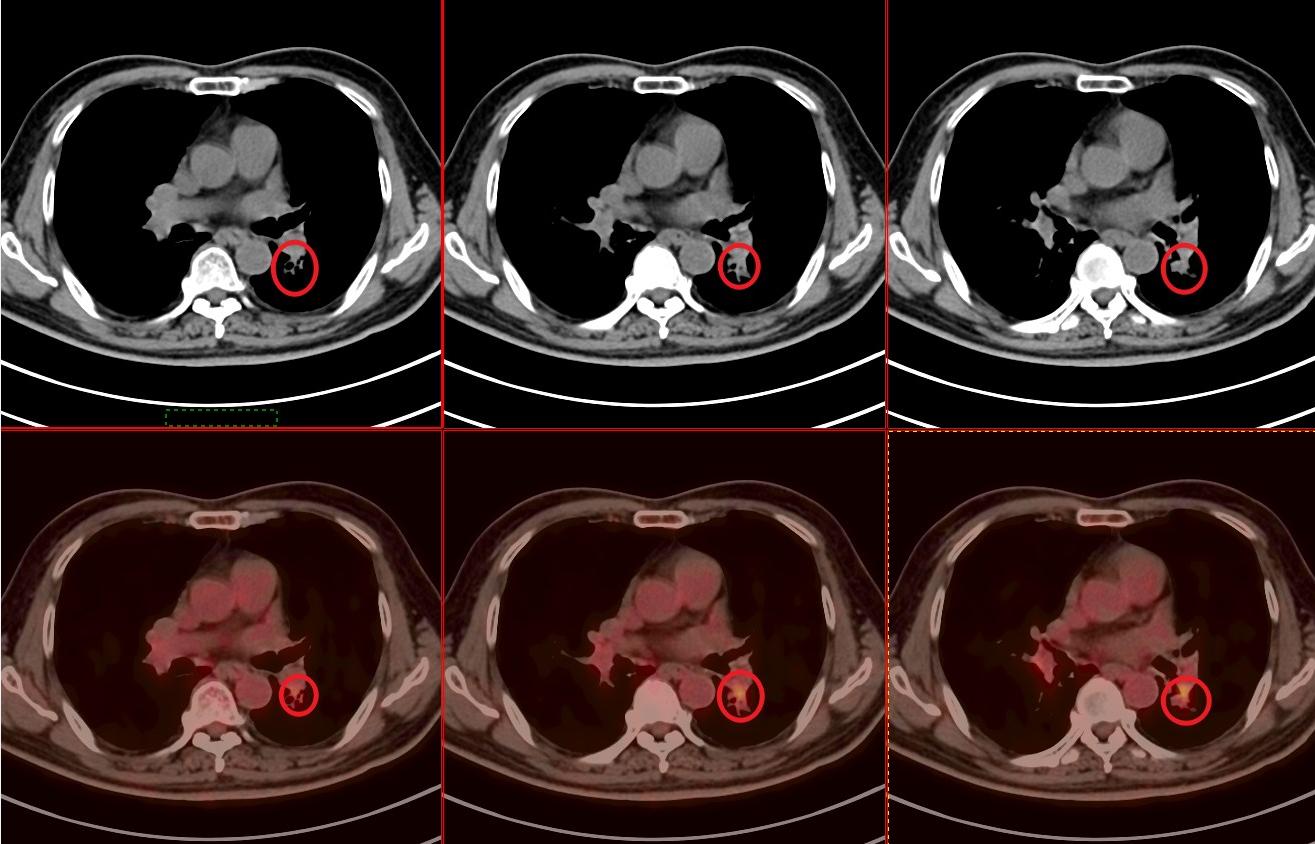

05. 4期治疗后复查, 今日来复查 :病灶明显缩小,FDG-PET/CT肿瘤活性明显减低。

病灶由最大4cm,缩小1.5cm,最重要的是肿瘤活性明显减低,SUV最大值由10.2,降低到3.0,病灶内还有少许肿瘤活性残留。